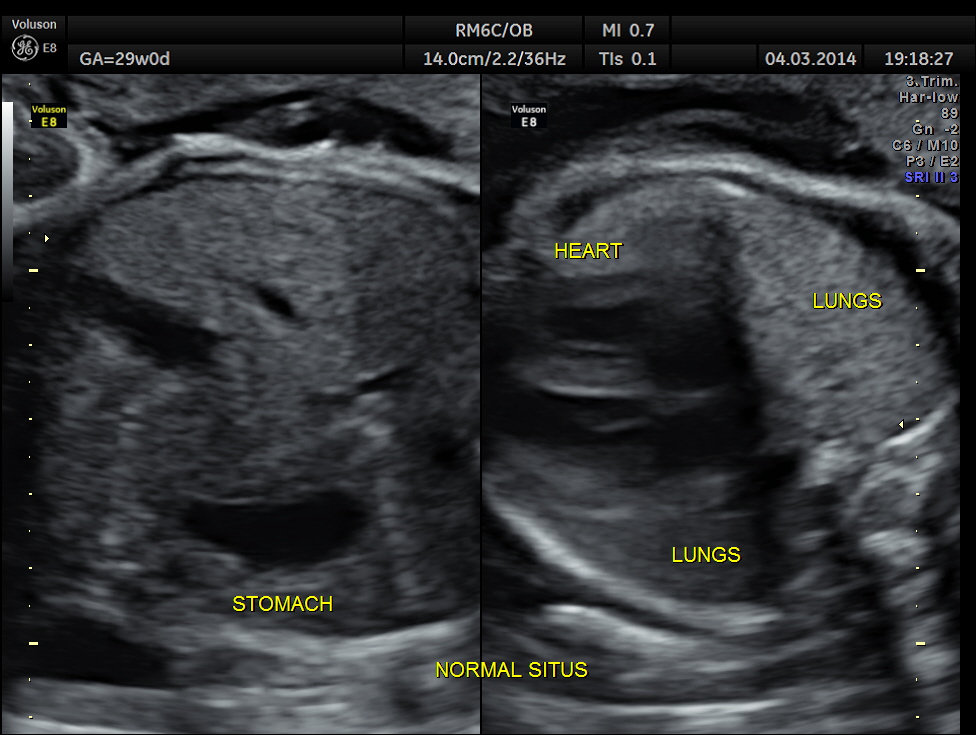

Images of the other organs are given below.